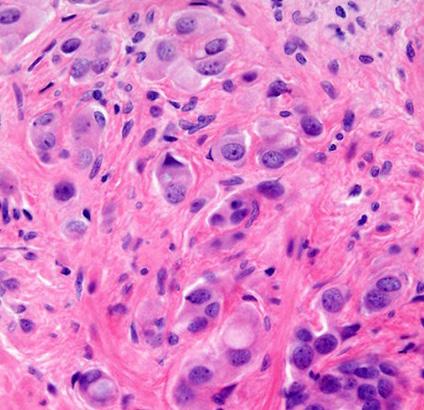

Anew UCLA study has found that artificial intelligence could help doctors identify prostate cancer patients most likely to benefit from targeted treatment that removes cancer while sparing healthy tissue, according to a UCLA-led study published Tuesday.

Researchers evaluated the new Unfold AI software that uses data from MRIs and biopsies to generate a detailed 3D map of prostate tumors. The study found that the AI technology's measurements of tumor size — compared with relying solely on tumor grade or prostate-specific antigen levels — significantly improved doctors' predictions of successful treatment.

"By using AI to measure the size of a man's prostate tumor more precisely, we can better predict who is likely to be cured with focal therapies like partial gland cryoablation," Dr. Wayne Brisbane, assistant professor of urology at UCLA's David Geffen School of Medicine,

said in a statement.

The study tested whether Unfold AI's tumorvolume mapping would aid doctors in predicting a patient's likelihood for successful outcomes from a treatment called "partial gland cryoablation," a minimally invasive procedure that freezes and eradicates only cancerous areas of the prostate instead of removing or irradiating the entire gland. The treatment minimizes damage to vital areas, which reduces side effects in an effort to maintain patients' quality of life, researchers found. Current methods of predicting treatment success — tumor grade and PSA levels — often underestimate tumor size can miss smaller cancerous areas, often leading to incomplete treatment and cancer recurrence.

"The study marks an important advance in integrating AI into prostate cancer treatment decisionmaking, offering the potential for more personalized prostate cancer care,"

Although the findings are promising, researchers emphasized the need for broader trials to validate the results.

“Such a method has not been previously available," Dr. Leonard Marks, professor and deKernion Endowed Chair in Urology UCLA's medical school, said in a statement. "It's important because tumor volume is a major determinant of treatment success or failure."

Marks, who is also a member of the UCLA Health Jonsson Comprehensive Cancer Center and senior author of the study, added, "Using AI to predict tumor volume and shape gives a clearer picture and could help choose better candidates for focal cryotherapy.”

Unfold AI was developed by researchers at UCLA and Avenda Health.

The study was published in BJUI Compass, a peerreviewed medical journal specializing in urology, and is available online at pmc. ncbi.nlm.nih.gov/articles/ PMC11771490.